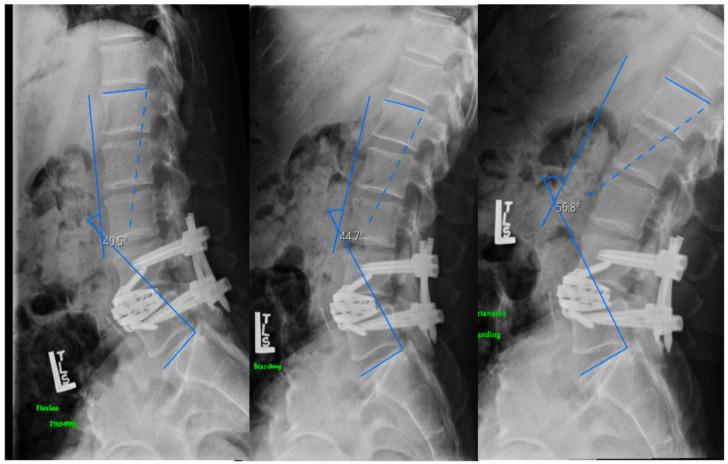

Loss of lumbar lordosis caused by single level degenerative spondylolisthesis can trigger significant sagittal plane imbalance and failure to correct lumbopelvic parameters during lumbar fusion can lead to poor outcome or worsening deformity. Anterior column release (ACR) through a pre-psoas approach allows the placement of a hyperlordotic cage (HLC) to improve lumbar lordosis, but it is unclear if the amount of cage lordosis affects radiological outcomes in real-life patient conditions. Three patients were treated with ACR and 30° expandable HLC for positive sagittal imbalance secondary to single-level spondylolisthesis. Patients reported baseline and post-operative Oswestry Disability Index (ODI) and Numeric Pain Score (NRS). Radiographic parameters of sagittal balance included lumbar lordosis (LL), sagittal vertical axis (SVA) and pelvic incidence-lumbar lordosis mismatch (PI-LL). Surgical indications were sagittal plane imbalance caused by L4-L5 degenerative spondylolisthesis (n = 2) and L3-L4 spondylolisthesis secondary to adjacent segmental degeneration (n = 1). Average post-operative length of stay was 3 days (range 2-4) and estimated blood loss was 266 mL (range 200-300). NRS and ODI improved in all patients. All experienced improvements in LL (x¯preop = 33°, x¯postop = 56°), SVA (x¯preop = 180 mm, x¯postop = 61 mm) and PI-LL (x¯preop = 26°, x¯postop = 5°). ACR with expandable HLC can restore sagittal plane balance associated with single-level spondylolisthesis. Failure to perform ACR with HLC placement during pre-psoas interbody fusion may result in under correction of lordosis and poorer outcome for these patients.

单节段退变性脊椎滑脱导致腰椎前凸丢失可引发明显矢状面失衡,如果在腰椎融合过程中不能纠正腰骨盆参数,可导致不良结果或畸形恶化。前路柱松解(ACR)经前路松解可使超前凸椎间融合器(HLC)的放置,从而改善腰椎前凸,但尚不清楚在现实患者情况下,椎间融合器的前凸角度是否会影响影像学结果。3 例单节段脊椎滑脱继发阳性矢状面失衡患者采用 ACR 和 30°可扩张 HLC 治疗。患者报告术前和术后 Oswestry 功能障碍指数(ODI)和数字疼痛评分(NRS)。矢状面平衡的影像学参数包括腰椎前凸(LL)、矢状垂直轴(SVA)和骨盆入射角-腰椎前凸不匹配(PI-LL)。手术指征为 L4-L5 退变性脊椎滑脱(n = 2)和 L3-L4 脊椎滑脱继发邻近节段退变(n = 1)导致的矢状面失衡。术后平均住院时间为 3 天(范围 2-4 天),估计失血量为 266 mL(范围 200-300 mL)。所有患者的 NRS 和 ODI 均改善。所有患者均改善了 LL(x¯术前=33°,x¯术后=56°)、SVA(x¯术前=180mm,x¯术后=61mm)和 PI-LL(x¯术前=26°,x¯术后=5°)。前路柱松解联合可扩张 HLC 可恢复与单节段脊椎滑脱相关的矢状面平衡。如果在前路融合过程中未能进行 ACR 和 HLC 放置,可能会导致前凸角度矫正不足,这些患者的结果较差。